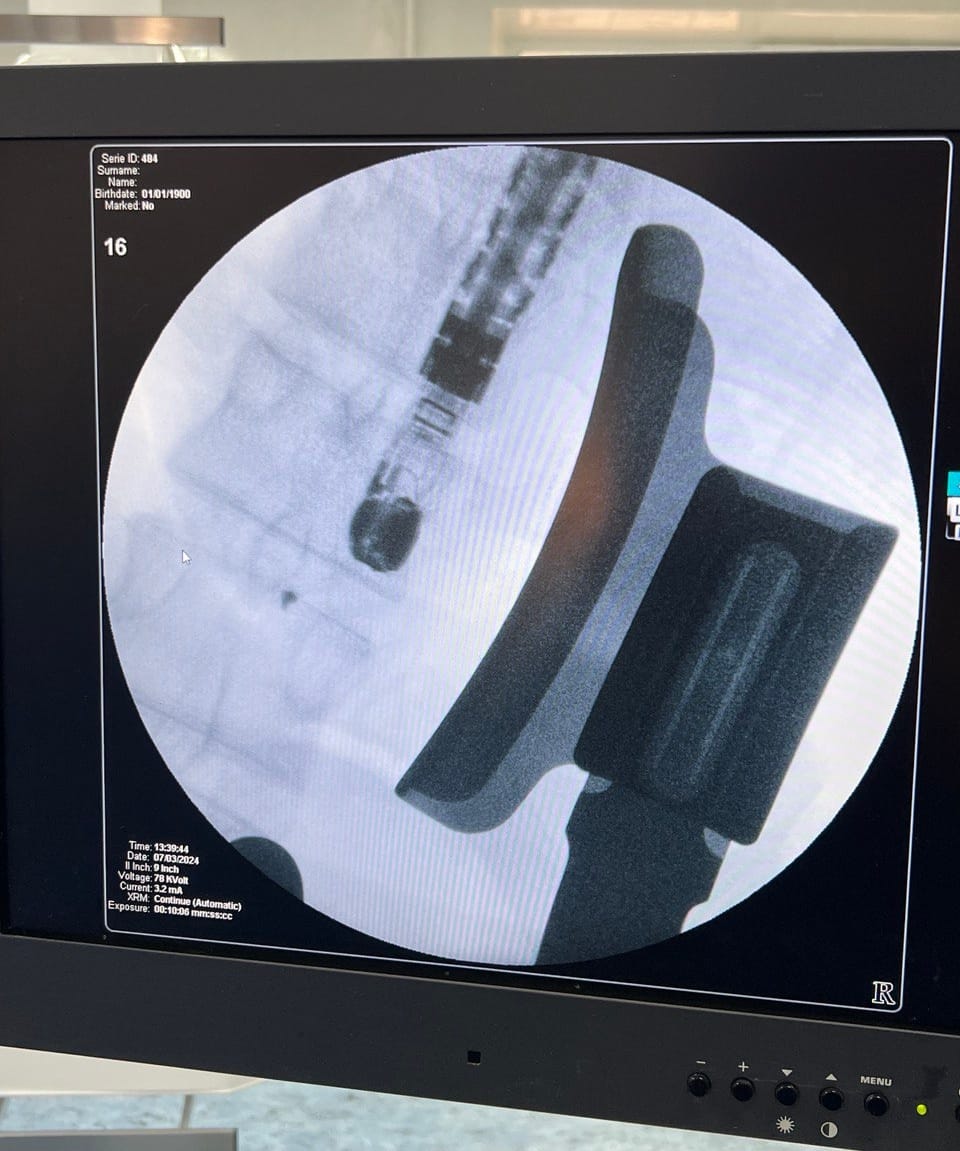

7 березня у Вінницькій «Пироговці» хірурги успішно провели надскладну операцію на працюючому серці пацієнта. Операція проводилась без зупинки кровообігу через міні-доступ з використанням сучасних методів рентгеннавігації та магнітних пристроїв.

Використання малоінвазивного методу міністернотомії дозволило зменшити об'єм хірургічної травми та період післяопераційної реабілітації, що відповідає сучасним світовим стандартам надання медичної допомоги.